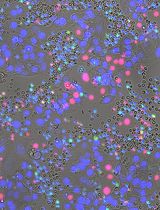

Neovascular diseases of the retina, such as diabetic retinopathy (DR) and age-related macular degeneration (AMD), are proliferative retinopathies involving the growth of new blood vessels on the retina, which in turn causes impairment and potential loss of vision. A drawback of conventional angiogenesis assays is that they are not representative of the angiogenic processes in the retina. In the retina, the new blood vessels grow (from pre-existing blood vessels) and migrate into a non-perfused region of the eye including the inner limiting membrane of the retina and the vitreous, both of which contribute to vision loss. The Matrigel Duplex Assay (MDA) measures the migration of angiogenic capillaries from a primary Matrigel layer to a secondary Matrigel layer, which resembles the pathological angiogenesis in AMD and DR. The methodology of MDA is comprised of two steps. In the first step, the human retinal microvascular endothelial cells (HRMECs) are mixed with phenol red–containing Matrigel (in a 1:1 ratio) and seeded in the center of an 8-well chamber slide. After 24 h, a second layer of phenol red–free Matrigel is overlaid over the first layer. Over the course of the next 24 h, the HRMECs invade from the primary Matrigel layer to the secondary layer. Subsequently, the angiogenic sprouts are visualized by brightfield phase contrast microscopy and quantified by ImageJ software. The present manuscript measures the angiogenesis-inhibitory activity of the Src kinase inhibitor PP2 in primary HRMECs using the MDA. The MDA may be used for multiple applications like screening anti-angiogenic drugs, measuring the pro-angiogenic activity of growth factors, and elucidating signaling pathways underlying retinal angiogenesis in normal and disease states.

The MDA represents a combination of all the steps of retinal angiogenesis and provides a highly relevant model for the study of pro- and anti-angiogenic agents in vitro. In-depth morphological studies have shown that the angiogenic sprouting (occurring in the MDA) closely mimics retinal angiogenesis in vivo. Electron microscopy studies have demonstrated the presence of a lumen and elaborate cell–cell junctions within the endothelial cell aggregates observed in the MDA [9, 10]. As the endothelial capillary tube–like structures invade into the secondary Matrigel layer, the leading edge of the capillary sprouts is associated with long filopodia. The structure of these filopodia resembles those seen at the angiogenic front during developmental angiogenesis in the neonatal retina [9]. The retinal endothelial cells grown within the two layers of Matrigel reflect the biological characteristics of the neovascular retina, such as diffusion gradient of oxygen, nutrients, and pH. The growth of the cells inside the Matrigel duplex system allows for complex cell–cell and cell–matrix interaction. Furthermore, these retinal endothelial sprouts may be characterized and quantified by confocal microscopy [9].

We devised a novel strategy to clearly differentiate between the two Matrigel layers in the MDA by utilizing phenol red–free Matrigel (PR-free-Matrigel) and phenol red–containing Matrigel (PR-Matrigel) for the individual layers. Initially, we tried to use PR-free-Matrigel for the primary layer and PR-Matrigel for the secondary layer but found that this arrangement resulted in poor quality photographs under a microscope. Subsequently, we reversed the layers (using the PR-Matrigel in the primary layer and PR-free-Matrigel in the secondary layer) and obtained clearer pictures under phase contrast microscopy, providing readily reproducible images and assay results. The present manuscript describes the ability of the Src Kinase inhibitor PP2 [12] (at a concentration of 10 µM) to suppress retinal angiogenesis of human retinal microvascular endothelial cells (HRMECs) using our modified MDA protocol. We hope that the MDA will be a useful tool for researchers working in the field of physiological and pathological angiogenesis in the retina.